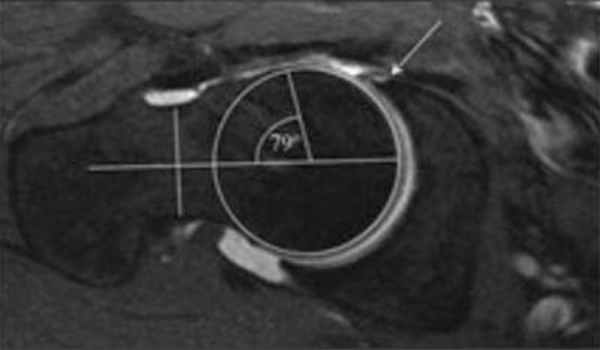

Признаки бедренно-вертлужного импиджмента на артрограмме

МРТ - исследование помимо признаков, которые мы видим на рентгенограммах, помогает нам оценить наличие свободной жидкости в полости сустава, а также повреждение мягкотканых компонентов сустава.